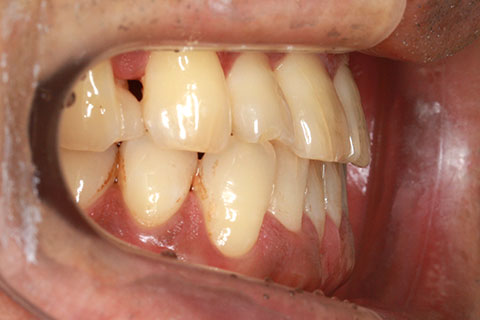

ハーフリンガル矯正4:上の歯のみ舌側矯正で治療(矯正期間24ヶ月)

- 年齢・性別

- 23歳女性

- 治療期間

- 2年0ヶ月

- 抜歯

- 上下4番抜歯

- 治療費

- 110万円

- 備考

- マルチブラケットを用いた矯正治療

- 治療内容

- 施術の副作用(リスク)

- 表側矯正と比較して、前歯のラビッティング(舌側傾斜)を起こしやすい。